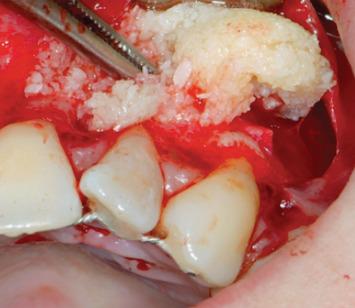

The aim of this case report was to evaluate the efficacy of a new platelet-rich plasma preparation and its regenerative capacity of bone periapical tissue for the treatment of a very compromised endodontic treated tooth, with a periapical lesion of 1.5 cm in diameter, using a pure platelet concentrate. This is made without the use of anticoagulant or any type of activator, e.g., bovine thrombin, calcium chloride. For this reason, it has been called "Pure"; it is the B.P.F.C.® Bio-Plasma® with Pure Growth Factors (BioPlasma®) designed and developed by Dr. Raffaello Viganò. The patient has read and signed a written consent form. The study protocol was approved by the Ethics Committee for Human Studies, University of Varese. X-ray at 2 and 6 months and 4 years after endodontic surgery demonstrated the success of the treatment.

本病例报告的目的是评估一种新型富血小板血浆制剂的疗效及其对根尖周组织的再生能力,该制剂为纯血小板浓缩物,用于治疗一颗根管治疗后严重受损且根尖周病变直径达1.5厘米的牙齿。该制剂的制备不使用抗凝剂或任何类型的激活剂,如牛凝血酶、氯化钙。因此,它被称为“纯”;它是由拉斐尔洛·维加诺博士设计和研发的含有纯生长因子的B.P.F.C.®生物血浆®(BioPlasma®)。患者已阅读并签署了书面知情同意书。该研究方案已获得瓦雷泽大学人体研究伦理委员会的批准。根管治疗术后2个月、6个月和4年的X线检查显示治疗成功。